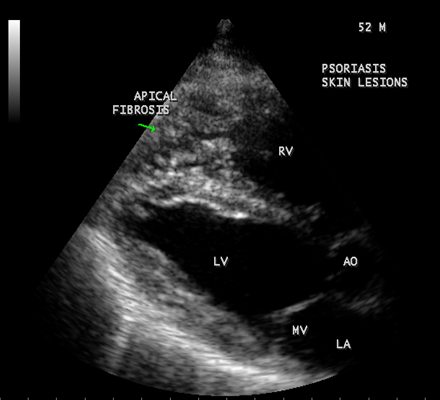

Transthoracic echocardiography revealed strong fibrous strands appearing as ‘finger like projections’ or ‘cobra-head’ appearance in the right ventricular apex due to fibrosis of muscular trabeculae, suggesting right ventricular endomyocardial fibrosis as shown in Figures 3 to 7.

Figure 5: Parasternal long axis view showing the RV (right ventricular) apical fibrosis in a 52-year old male with psoriasis

Figure 6: Dense fibrosis in RV apex in Psoriasis in a 52-year old male.